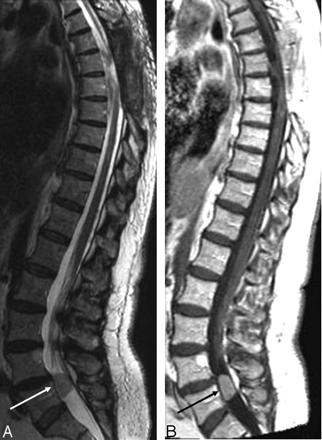

The images (Fig 1) demonstrated an extramedullary lesion, posteriorly located and extending from T5–T6 to T8, compressing the spinal cord anteriorly. The axial images (Fig 2) were the most useful in demonstrating the extramedullary location. The lesion was well defined, with some septa inside. It was essentially isointense with the CSF on all pulse sequences. The adjacent spinal cord was abnormal on T2-weighted sequences with a hyperintense appearance (T5–T6) (Fig 1A,-B). After gadolinium injection (Fig 1C,-D), there was no enhancement of the cystic extramedullary lesion. No enhancement was seen within the spinal cord, but the cord surface was covered by a rich vascular, enhancing network, probably because of the compression of the venous plexus system. No other abnormalities were found within the brain or in the spinal cord. The final preoperative diagnosis was arachnoid cyst with spinal cord compression.

Preoperative MR imaging. Sagittal T2- (A and B) and T1-weighted images before (C) and after (D) gadolinium injection. It is extremely difficult to determine whether this lesion is intra- or extramedullary. No contrast enhancement is seen. Septa are observed within the lesion.

Sagittal T2-weighted (A) and T1-weighted gadolinium-enhanced (B) images obtained after a second surgery showing the total removal of the anteriorly located cystic lesion. Persistent spinal cord hypersignal intensity is seen in T2-weighted image (arrow).